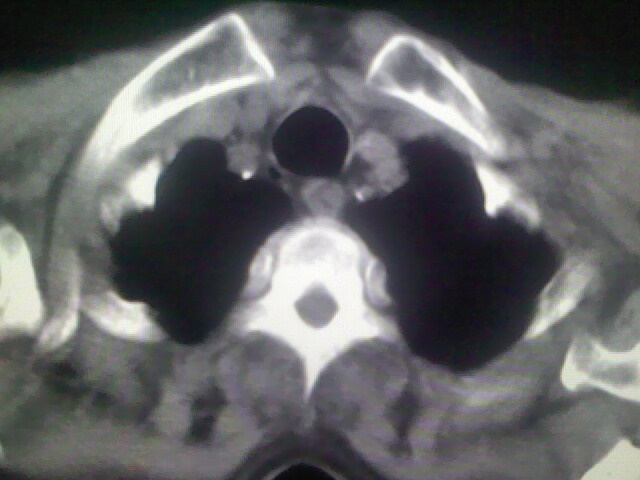

1)考虑右肺上叶周围型肺癌并纵隔及右颈部淋巴结转移,肝脏多发性转移。2)肺气肿。3)冠状动脉及主动脉钙化。

1)考虑右肺上叶周围型肺癌并纵隔及右颈部淋巴结转移,肝脏多发性转移。2)肺气肿。3)冠状动脉及主动脉钙化。支持!另:胃内病变不好确定,建议行胃镜!

资料不清晰啊,肺内病灶内可见多发钙化影,结核不能除外.肝内符合转移瘤表现.既然楼主提供胃内占位,那原发灶还是考虑来源于胃腔.

1)考虑右肺上叶周围型肺癌并纵隔及右颈部淋巴结转移,肝脏多发性转移。2)肺气肿。3)冠状动脉及主动脉钙化。胃未充盈而且影像不太清楚,不好确定